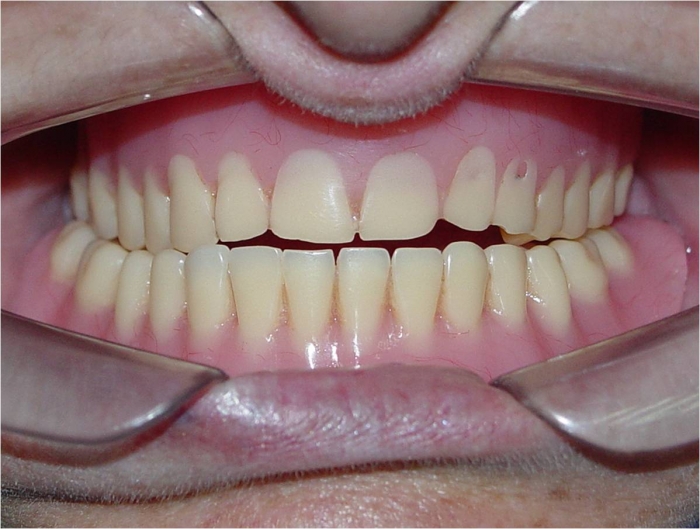

Imagem inicial

Sorriso inicial